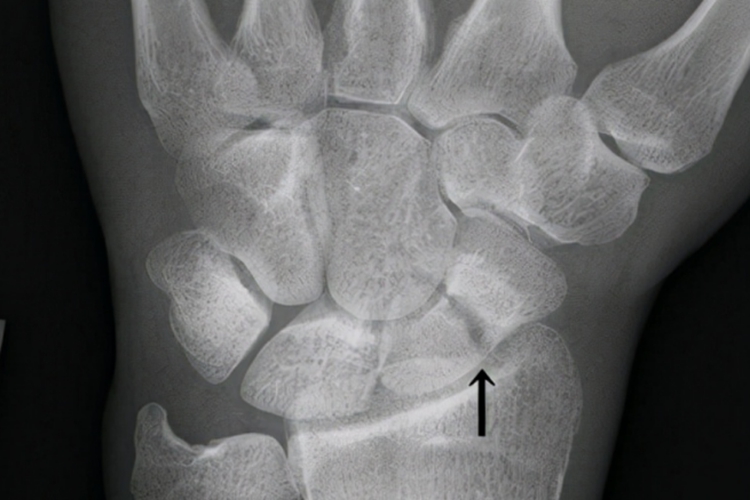

腕舟状骨骨折

腕舟状骨骨折是腕部骨折中最常见的骨折,按骨折部位分为舟骨远1/3骨折(关节内、外)、中1/3骨折、近端骨折。